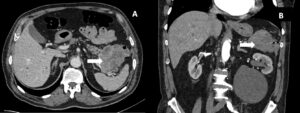

A 74-year-old male with previous history of diverticulosis presented to the emergency department for the third time in a month with complaints of hematochezia. Patient reported a 10kg weight loss in the past month. Blood test results revealed hemoglobin 11.7g/dL. Colonoscopy showed an elevated 30mm lesion with central mucosal disruption and active bleeding, located at the splenic flexure of the colon (Fig 1A-B). Endoscopic hemostasis was achieved with diluted adrenaline, through-the-scope clips, and hemostatic powder (Fig 1C-D). Biopsies were performed but inconclusive. CT angiography revealed a 7.5 x 5.5 cm lobulated, exophytic lesion with peripheral enhancement and central hypodense areas, extending from the transverse colon and in direct contact with the pancreatic tail (Fig2). This also showed perilesional adenopathies and multiple liver metastases.

Figure 2: Transverse (A) and sagittal (B) CT images showing a lobulated, exophytic lesion (arrow) with peripheral enhancement and central hypodense areas, extending from the transverse colon and in direct contact with the pancreatic tail